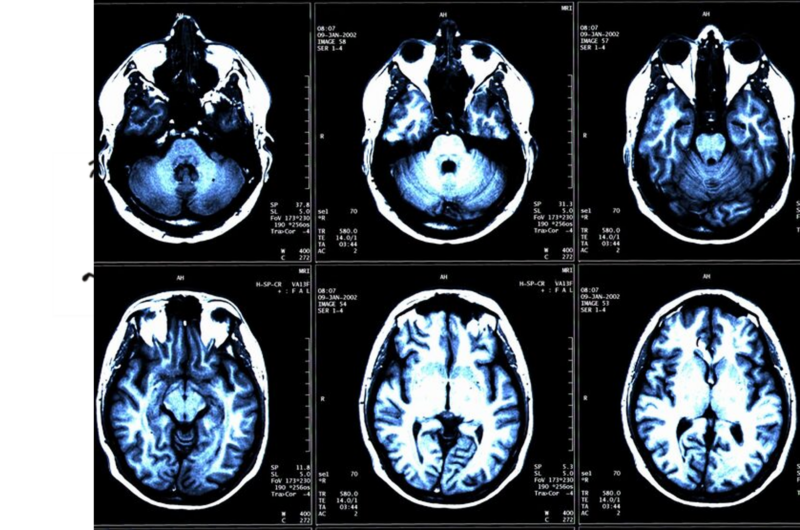

Forscher am Max-Planck-Institut sollen herausgefunden haben, dass eine MRT-Aufnahme des Gehirns im Vorschulalter zeigen kann, ob ein Kind an einer Lese-Rechtschreibschwäche leidet. „Die Autoren empfehlen, diese Ergebnisse zur Früherkennung einer Legasthenie zu nutzen.“ Ich bin gespannt, was daraus wird, zumal eine Trefferquote von 75 Prozent angegeben wird. Also, ganz sicher ist die Sache nicht. Der für die Untersuchung ausgezeichnete Wissenschaftler, Dr. Michael Skeide, sagt: „Je früher eine Legasthenie erkannt wird und die betroffenen Kinder eine entsprechende Förderung erhalten, desto größer ist die Chance, dass die Ausprägung der Störung deutlich abgeschwächt werden kann“. Ja, aber: …